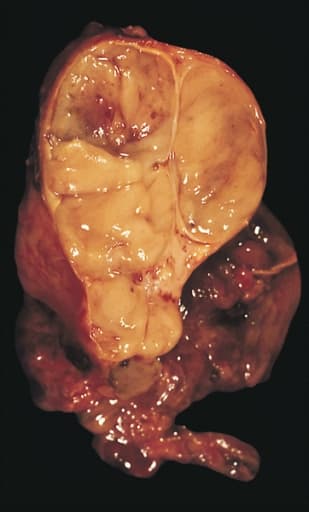

A thymoma is a tumor originating from the epithelial cells of the thymus that is considered a rare malignancy. Thymomas are frequently associated with neuromuscular disorders such as myasthenia gravis; thymoma is found in 20% of patients with myasthenia gravis. Once diagnosed, thymomas may be removed surgically. In the rare case of a malignant tumor, chemotherapy may be used. A third of all people with a thymoma have symptoms caused by compression of the surrounding organs by an expansive mass. These problems may take the form of superior vena cava syndrome, dysphagia (difficulty swallowing), cough, or chest pain. One-third of patients have their tumors discovered because they have an associated autoimmune disorder. As mentioned earlier, the most common of those conditions is myasthenia gravis (MG); 10–15% of patients with MG have a thymoma and, conversely, 30–45% of patients with thymomas have MG. Additional associated autoimmune conditions include thymoma-associated multiorgan autoimmunity, pure red cell aplasia and Good syndrome (thymoma with combined immunodeficiency and hypogammaglobulinemia). Other reported disease associations are with acute pericarditis, agranulocytosis, alopecia areata, ulcerative colitis, Cushing's disease, hemolytic anemia, limbic encephalopathy, myocarditis, nephrotic syndrome, panhypopituitarism, pernicious anemia, polymyositis, rheumatoid arthritis, sarcoidosis, scleroderma, sensorimotor radiculopathy, stiff person syndrome, systemic lupus erythematosus and thyroiditis. One-third to one-half of all persons with thymoma have no symptoms at all, and the mass is identified on a chest X-ray or CT/CAT scan performed for an unrelated problem. Thymoma originates from the epithelial cell population in the thymus, and several microscopic subtypes are now recognized. There are three principal histological types of thymoma, depending on the appearance of the cells by microscopy: Type A if the epithelial cells have an oval or fusiform shape (less lymphocyte count); Type B if they have an epithelioid shape (Type B has three subtypes: B1 (lymphocyte-rich), B2 (cortical) and B3 (epithelial).